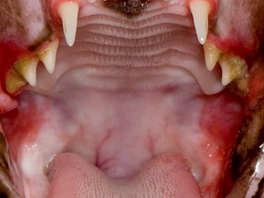

5. 고양이 만성 구내염

완치가 어려운 고양이 치과 질환 중 하나입니다.

잇몸뿐 아니라 구강, 목구멍까지 광범위한 염증과 통증이 동반됩니다.

주요 증상: 식욕 부진, 통증

치료: 약물 치료 + 발치

마이캣클리닉에서는 재발을 줄이기 위해

구강 엑소좀 치료, 인터페론 치료 등을 병행하고 있습니다.

6. 구강 종양

고양이 구강 종양은 악성 비율이높은 편입니다.

정확한 진단을 위해 세포검사가 필요하며

레이저·고주파 수술기구 또는 구강 외과적 수술이 필요할 수 있습니다.